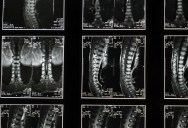

According to the World Health Organisation, around 15 million people worldwide are living with spinal cord injuries.

These injuries can be debilitating and disabling, with significant risk of potentially life-threatening secondary conditions resulting from mostly preventable injuries.

Through a long-term research program led by Professor Hideyuki Okano, the team have developed a stem-cell treatment for spinal cord injuries, using induced pluripotent stem (iPS) cells – adult cells that have been manipulated to resemble embryonic ones.

With the transplantation of these iPS cells into four patients who had recently sustained spinal cord injuries, Okano and his team claim to have a fifty percent success rate of patients regaining motor function with the treatment and rehabilitation – considerably more than the numbers regaining it from rehabilitation alone.

As Japanese newspaper The Asahi Shimbun reports, the trial took place over a year, during which time patients who had injured their spinal cords within the last two to four weeks were injected with the cells at the site of injury.

After a year of observations, it was concluded that the patients had suffered no adverse effects from the treatment, and the fifty percent success rate even included one of the patients regaining the ability to stand with the use of a support mechanism.

Though the news that one patient regained the ability to stand – and is now learning how to walk once more – is promising, it should be noted that this was an extremely small trial.

Next, the treatment will be tested more widely, to ensure that the cells are indeed safe and effective before more widespread treatment can be rolled out.